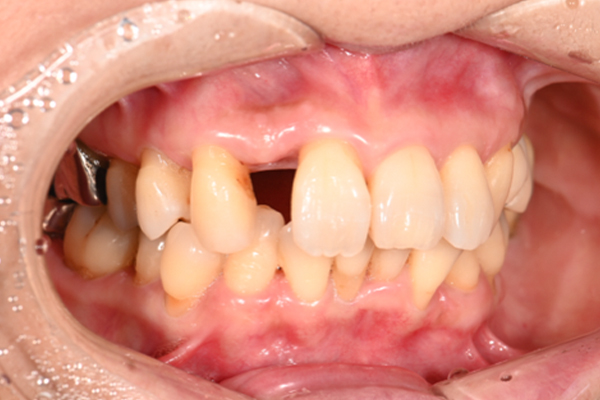

| 主訴 | 全体的にきれいにしたい |

| 治療内容 | 午前中に上下顎共に重度の歯周病、虫歯のため全ての歯を抜歯させていただき下顎はインプラントの土台を3本埋入し歯型を取り午後に上部構造(下顎全ての歯)を装着、上顎は一度総入れ歯を装着させていただきました。 治療が1日で完了しその日のうちに噛めるようになります。 |

| 治療期間 | 2回(1回目に資料取りをさせていただき2回目に下記の全ての治療をさせていただきました。) |

| 治療費 | 250万円 |

| 治療 リスク | 抜歯した部位などに関しては当日痛みが出ますので痛み止めなどを処方させていただきます |